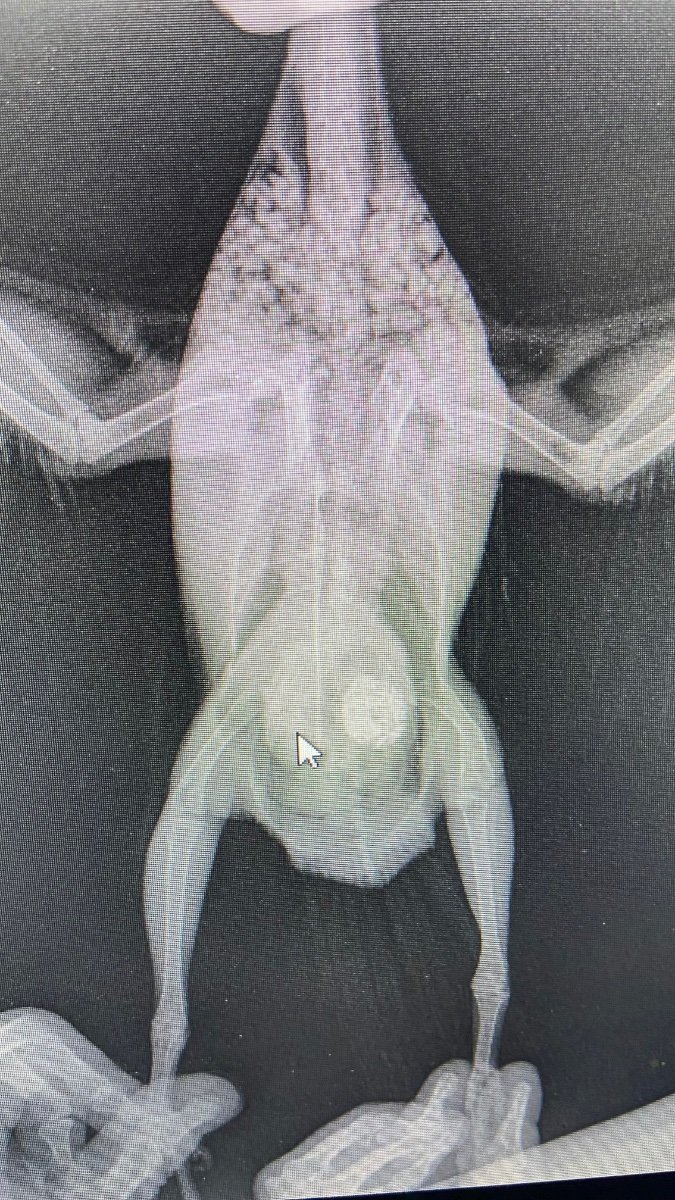

Simon.S Опубликовано 29 ноября, 2023 Автор #22 Опубликовано 29 ноября, 2023 @KatinPtic По рентгену определили, что у птенца деформация бедра и пальцев левой кисти как следствие гнездовой травмы. скорее всего более сильный птенец давил весом или как-то иначе. Пацы подлежат ампутации. Но пока рано. У него увеличена печень, есть какое-то образование вокруг, проблемы с почками. Возможно это из-за длительного приема антибиотика для лечения микоплазмоза. Для поддержания печени не давалось ничего. Сейчас назначено лечение на 2 месяца. Потом снова на рентген и дальше видно будет. Фото прикладываю. @KatinPtic 1

Simon.S Опубликовано 29 ноября, 2023 Автор #24 Опубликовано 29 ноября, 2023 @маленький принц Нет, не стала. Орнитолог сказал, что это может быть. У него же вся сторона деформирована. По осмотру это не фоликуллез. Перья растут криво, так как кости пальцев как-будто смяты. Да и фото сделано телефоном с компьютера, так плохо видно.

KatinPtic Опубликовано 29 ноября, 2023 #25 Опубликовано 29 ноября, 2023 @Simon.S хорошо, что к вет-орнитологу поехали! Вопрос, почему именно к Никите? Я без всяких там - просто почему именно к нему? Посоветовал кто-то? Были уже у него? Я для себя спрашиваю, чтобы самой понимать, потому что на сайте рекомендованные - я была у многих и рекомендовать бы их не стала. По лабораторному исследованию - взяли только кровь? Больше никаких материалов и анализов не будет? Про ампутацию - подождите еще, там же написано "в перспективе, возможно" - прямых показаний-то нет пока. Продублируйте все Зосе, пусть она скажет свое мнение, в том числе и по назначению. Местная обработка кисти крыла в назначении касается только кожных покровов, а сама причина - она как бы никуда не денется и нет вообще никаких противовоспалительных препаратов, нет обезболивающего - хотя явно при таком "повреждении" оно как бы все напрашивается. Вероятно, он говорил об этом на приеме , при этом добавляя - давайте пожалеем печень и пусть птичка потерпит. Но воспалительный и болезненный процессы как-то не принято игнорировать. А эти процессы они же явно присутствуют. Касаемо кровотечения постоянного , где перья растут "неправильно" - тоже ничего. Ну это как бы все стоило бы уточнить, хотя бы крапиву добавить что ли, я уж не говорю, что тут такие кровотечения бывают, кроме фонтанировать не назовешь и Вы должны знать, как их останавливать, медикаментозно в том числе. Не оставляйте этот вопрос без Вашего внимания. Ну извините, пожалуйста. Указывать "предположение" в утвердительной форме - в случае с этим голубочком- как гнездовая травма - это не диагноз. Короче, это вызывает вопросы. Пожалуйста, отнеситесь к моему сообщению не как желание раскритиковать назначение и вцелом прием у доктора. А просто считаю нужным - уточнить эти моменты. Можно было и у самого Никиты, кстати, спросить. Посоветуйтесь с Зосей. Не только по тому, что я Вам написала, а вцелом. 21 минуту назад, Simon.S сказал: По осмотру это не фоликуллез. Нет. Это именно Полифолликулез. Полифолликулез - это порок развития фолликула, при котором в одном фолликуле растет несколько перьев . Зося же Вас правильно направила на рентген: установить причину этого явления, почему же перья растут из одного фолликула? Причину Вам и установили - поражение левой кисти. То есть , что имеем теперь? Имеем Полифолликулез - вторично, первично - вот то самое поражение кисти. Стоило бы с Зосей посоветоваться. В 25.11.2023 в 22:12, Simon.S сказал: Вот, здесь. То есть в случае с Вашим голубочком - травматика. Понимаете, ампутация - это край, как правило, ветеринары -орнитологи до последнего бьются за то, чтобы птица осталась птицей, сохранить крылья и их работоспособность. Тут же в назначении и в перспективах- ну ничего вообще не сказано про то, чтобы как-то облегчить ситуацию с крылом. Это честно, это надо 300 раз взвесить все "за" и "против" . Конечно, очень цинично будет звучать здесь следующее : "7 разь отмерь и один раз отрежь"... Но! Как никогда эта фраза звучит к месту в буквальном смысле. Проконсультируйтесь ещё поэтому голубю. Чего-то цитата не прикрепилась: вот здесь В 25.11.2023 в 22:15, KatinPtic сказал: Зося сказала, что фолликулез, но надо знать причину - инфекционная или травматическая Я вот про это пишу. 1

Simon.S Опубликовано 13 декабря, 2023 Автор #45 Опубликовано 13 декабря, 2023 @KatinPtic Здравствуйте. Попробую точно описать то, что я поняла из объяснений Зоси. По показаниям печени (из анализа крови) может быть новообразование в печени, а может костная ткань. По альбуминам в анализе - либо из-за почек они сильно повышены, либо из=за некорректной работы организма вследствие опухоли. При этом на рентгене почки не видны. А на сердце заметны какие-то гранулемы. В целом анализ крови показывает наличие в организме активного процесса распада ткани, в том числе мускульной (это может быть крыло, может сердце). В крыле 95 %, что идет инфекционный процесс, но удалять эту часть не нужно. В итоге Зося назначила по печени и почкам следующее: Гепатовет. 0,1 на каждые 60 - 80 г веса. У меня уже куплен гептрал (по предыдущему назначению), поэтому пока даю его. Из расчета 1/8 2 раза в день. Он же сильнее? Нам назначили 1/4, но я не рискнула так много. Урсосан. 7 мл на 100 г веса. Итого (вес 260 г) 18 мг. Капсулы на 250 мг, высыпаю и делю на части. Сложно, очень маленькая доза. Это 1 раз в день я даю. Цитостат. Его только получила, проблема с пунктом выдачи была, пришлось дважды оформлять, а доставка долгая была. Дозировка 1/2 таблетки + 2 мл воды и отсюда на наш вес 0,325 мл. 1 раз в сутки. Теперь дальше. Для крыла. Остеогенон я купила. Цефтриаксона в ближайших аптеках не было. Сегодня буду еще искать. У меня есть физраствор. Он подойдет для уколов? Шприцы все есть, разные, еще куплю, если закончатся. Мелоксикам ему нельзя, сказала Зося (из-за печени). Но можно ибупрофен и целикоксид (потом, если понадобится). Вот такие сейчас дела. По внутренним органам буду давать три препарата. Скажите, что думаете на счет гептрала. Можно ли сейчас давать его, а когда он закончится - гепатовет? Курсы препаратов долго - около года (Зося сказала). Что посоветуете начать для крыла. Уже много времени прошло, пока собирали эти препараты. Хочу поскорее начать лечение, надеюсь спасти это крылышко. Фото прилагаю. 4 часа назад, KatinPtic сказал: Как Зося прокомментировала, что сердцем что-то? Зося спрашивала дополнительное что-то? Что она вообще сказала про сердце? На что она опиралась? Сказала, что какие-то гранулемы, но не понятно, что это может быть. Может плохой снимок. 4 часа назад, KatinPtic сказал: Пролечить "месяц-полтора" - это Зося так назначила? Это я так решила, а потом сделать анализы. Но может и рано еще будет. Но лечение не прекращать. 4 часа назад, KatinPtic сказал: Это длительно достаточно, она говорила что-то про пересчет дозировок , например, при изменении веса птицы? Не говорила. Но я перевзвешиваю для корректировки. Пока вес не изменяется. Сам он клюет, но, боюсь, что мало. И есть выборочно, не все под ряд. Клюет канареечное семя, льняное и сафлор с охотой - остальное игнорирует. Поэтому когда даю лекарства, я докармливаю его сухой смесью зерна, водой запивает. 4 часа назад, KatinPtic сказал: Есть ли подозрение на хроническое, в отношении голубя - печень та же самая? Зося сказала, что такие показатели не могут быть из-за приема антибиотика без поддержки печени. Это скорее врожденное. 12 часов назад, KatinPtic сказал: Вы про какие лекарства тут спрашиваете? Те, что уже даёте? Или про те, что "с чередованием"? Про чередование - оптимальнее всего начать с антибиотика, затем добить патологию НПВС. Те, что даю, я поняла - для печени и почек. Но для крыла, для его лечения, я не понимаю, что конкретно каждое лекарство делает, т.е. На что оно влияет и для чего необходимо. Теперь мне нужно понять, что еще надо купить помимо цефтриаксона. 13 часов назад, KatinPtic сказал: Сначала купите препараты, Ибупрофен не надо, самое простое Мелоксикам ампульный, Мелоксикам ему нельзя, Зося сказала, из-за печени. Тогда ибупрофен? У него дозировка в продаже одна?